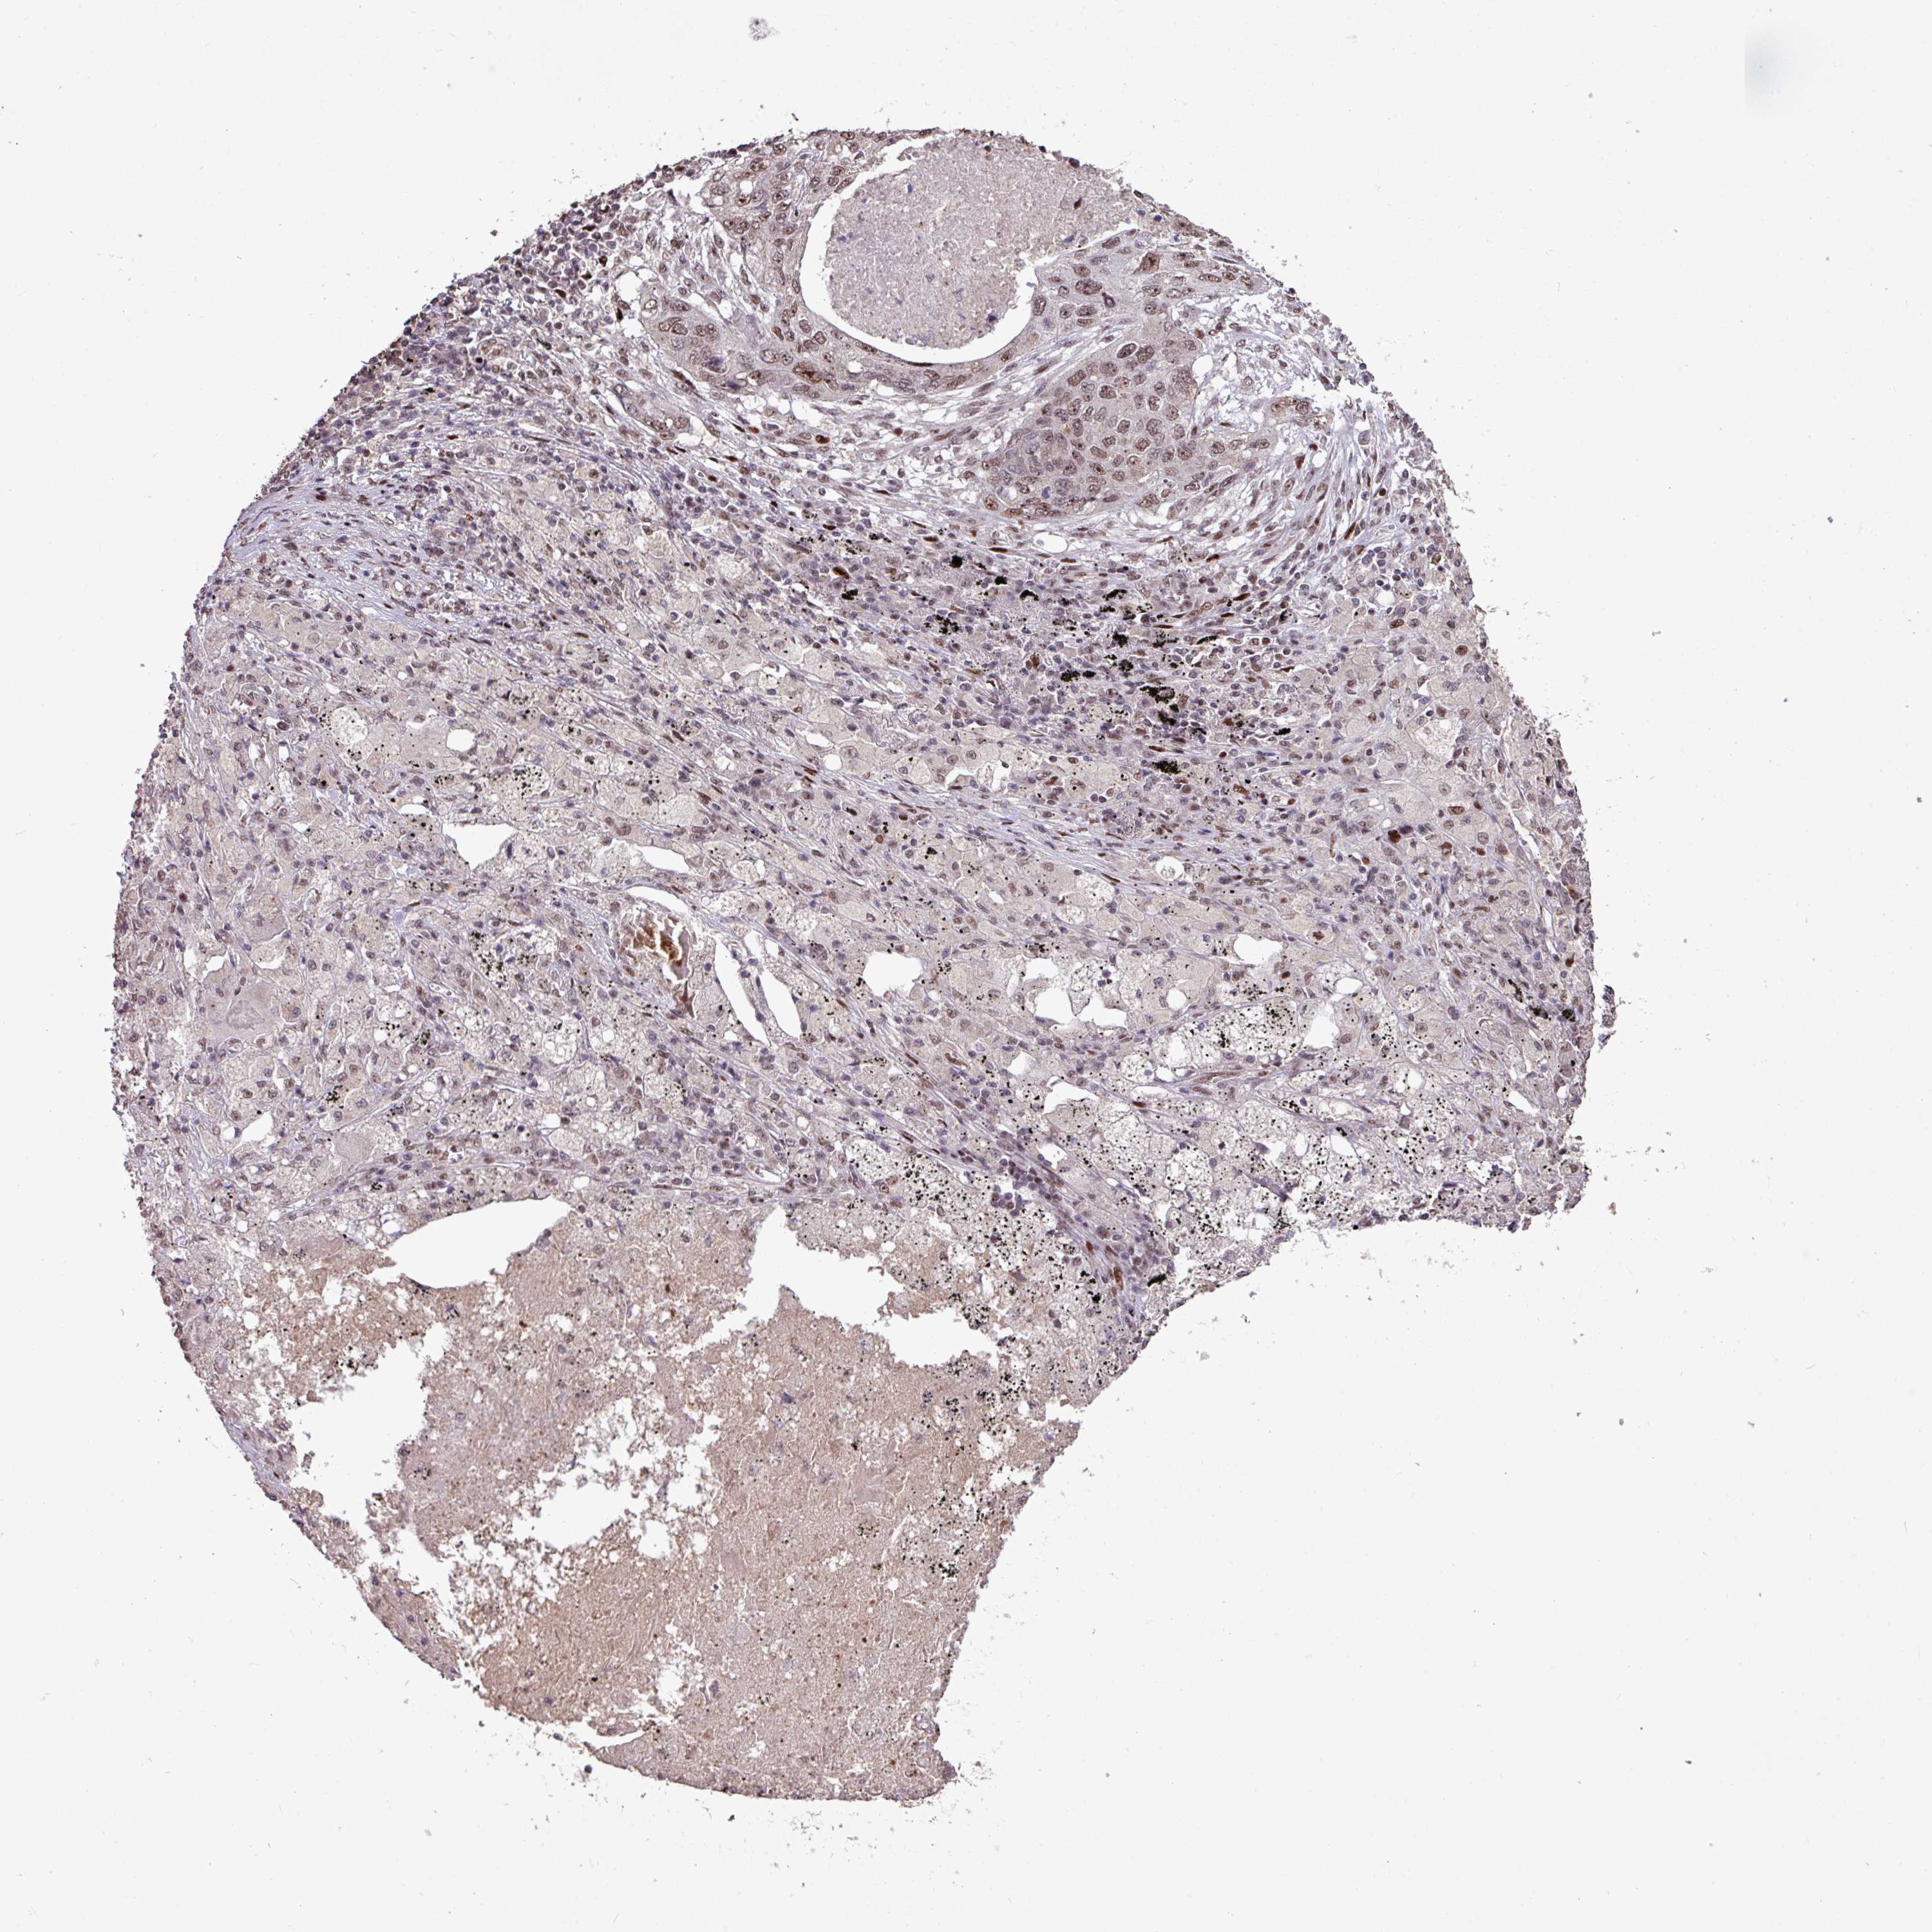

LUNG SQUAMOUS CELL CARCINOMA (TCGA) - Interactive survival scatter ploti

The Survival Scatter plot shows the clinical status (i.e. dead or alive) for all individuals in the patient cohort, based on the same data that underlies the corresponding Kaplan-Meier plots. Patients that are alive at last time for follow-up are shown in blue and patients who have died during the study are shown in red.

The x-axis shows the expression levels (FPKM) of the investigated gene in the tumor tissue at the time of diagnosis. The y-axis shows the follow-up time after diagnosis (years). Both axes are complimented with kernel density curves demonstrating the data density over the axes. The top density plot shows the expression levels (FPKM) distribution among dead (red) and alive patients (blue). The right density plot shows the data density of the survived years of dead patients with high and low expression levels respectively, stratified using the cutoff indicated by the vertical dashed line through the Survival Scatter plot. This cutoff is automatically defined based on the FPKM cutoff that minimizes the p-score. The cutoff can be changed by dragging the vertical line or by entering a cutoff value in the square labeled "Current cut-off".

Under the Survival Scatter plot the p-score landscape (black curve; left axis) is shown together with dead median separation (red curve; right axis). Dead median separation is the difference in median mRNA expression between patients who have died with high and low expression, respectively. It is calculated as follows: median FPKM expression of dead patients with high expression - median FPKM expression of dead patients with low expression. This is intended to aid the user in visually exploring custom cutoffs and the associated p-scores and dead median separation.

Individual patient data is displayed and can be filtered by clicking on one or more of the category buttons on the top of the page. Categories describing expression level and patient information include: high, low, alive, dead, female, male and tumor stages. The scale of the x-axis can be toggled between linear and log-scale by clicking on the "x log" button. Mouse-over function shows TCGA ID, patient information and mRNA expression (FPKM) for each patient.

& Survival analysisi

Kaplan-Meier plots summarize results from analysis of correlation between mRNA expression level and patient survival. Patients were divided based on level of expression into one of the two groups "low" (under cut off) or "high" (over cut off). X-axis shows time for survival (years) and y-axis shows the probability of survival, where 1.0 corresponds to 100 percent.

ZNF709 is not prognostic in Lung Squamous Cell Carcinoma (TCGA)

Best expression cut offi

Based on the FPKM value of each gene, patients were classified into two groups and association between prognosis (survival) and gene expression (FPKM) was examined. The best expression cut-off refers the FPKM value that yields maximal difference with regard to survival between the two groups at the lowest log-rank P-value. Best expression cut-off was selected based on survival analysis .

When clicking on this number, the vertical dashed line indicating cut-off, the interactive survival plot, and the Kaplan-Meier curve will be adjusted to show results based on the best expression cut-off.

: N/A

P scorei

Log-rank P value for Kaplan-Meier plot showing results from analysis of correlation between mRNA expression level and patient survival.

N/A

TCGA RNA samplesi

RNA-seq data is reported as average FPKM (number Fragments Per Kilobase of exon per Million reads), generated by the The Cancer Genome Atlas (TCGA) .

Normal distribution across the dataset is visualized with box plots, shown as median and 25th and 75th percentiles. Points are displayed as outliers if they are above or below 1.5 times the interquartile range. FPKM values of the individual samples are presented next to the box plot.

Average pTPM 0.7

Number of samples 489